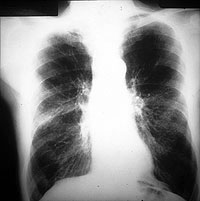

Esquema 36 Comentario placas 36 y 37 La placa corresponde a un gran fumador con enfisema pulmonar. Los lóbulos superiores y la base izquierda se ven más traslúcidos, por pobreza de vasos y los que hay son delgados y con ramificaciones escasas y distanciadas. Esta imagen es la constituye el signo radiológico específico de enfisema, que en la reproducción de la placa es poco evidente. Además los pulmones muestran signos de hiperinsuflación: aumento de volumen de los pulmones con diafragmas bajos y aplanados por debajo de la extremidad anterior de las costillas 7» u 8» y espacios intercostales dorsales horizontales y ensanchados En la placa lateral se aprecia el aplanamiento diafragmático y el aumento de contenido aéreo entre el esternón y el corazón. Si bien los signos de hiperinsuflación acompañan generalmente al enfisema no son específicos de éste y pueden observarse en otras obstrucciones bronquiales difusas como ser en el asma. Examine la placa 38 |